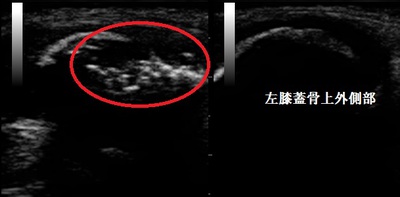

右膝蓋骨 超音波長軸像 左健側

数か月、走らないで様子を見ていましたが痛みは変わらず、当接骨院を受診されました。超音波検査の

結果、右膝蓋骨上外側部に骨の連続性が断たれた不正像が認められました(画像の赤丸の囲み)。

男子はお皿の骨の上外側部に分裂部があり、Ⅲ型と判明しました(下の分類図をご参照ください)。